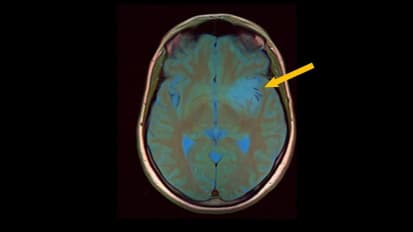

Researchers Identify Inflamed Brain Cells Likely Involved in MS Nerve Degeneration

MRI scans of a patient’s brain showing the chronic active lesions (areas of localized damage marked by arrows within magnified insets) associated with multiple sclerosis (MS). Johns Hopkins Medicine and National Institute of Neurological ...